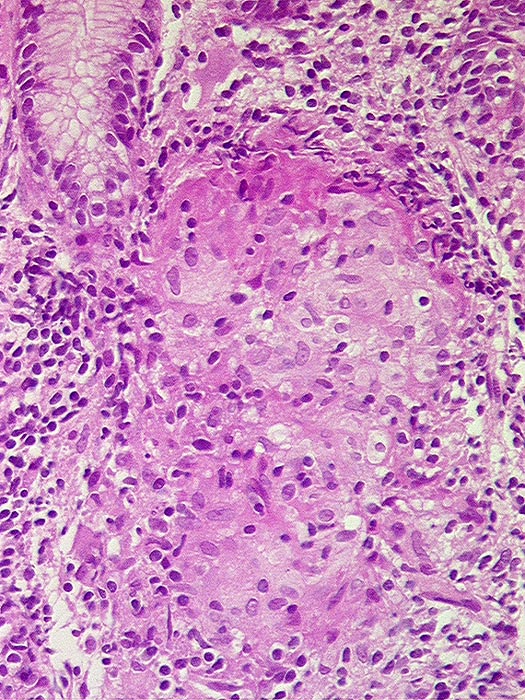

PathoPic ID 1284 - Morbus Crohn : Granulom

Morbus Crohn : Granulom

Entzündung / Reparatur

Magenkorpus

Oesophagus, Magen

Chronisches Entzündungsinfiltrat mit epitheloidzelligem Granulom.

Magenantrum ohne Befund.

Histologie